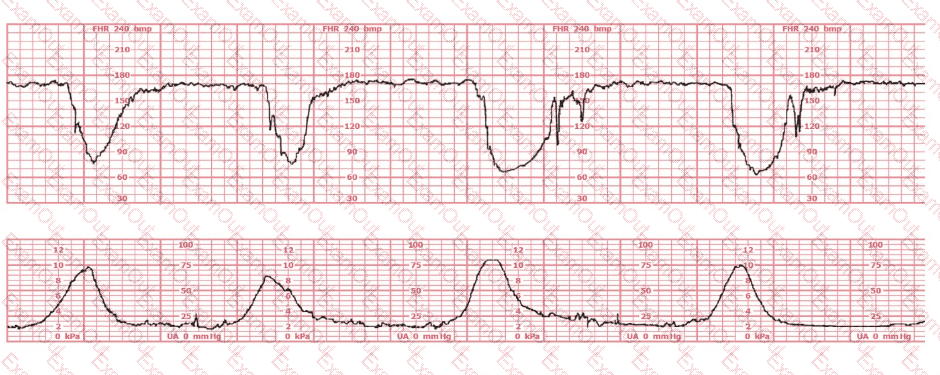

Baseline:

The fetal heart rate baseline is approximately 150 bpm, which is within the normal range of 110–160 bpm.

Variability:

The tracing shows minimal variability (approximately 1–4 bpm amplitude). Minimal variability for a sustained period is categorized as a Category II pattern under NCC/NICHD classification.

Accelerations:

No accelerations are present during the 20-minute representative segment.

Decelerations:

There are no recurrent variable, no recurrent late, and no prolonged decelerations.

Uterine Activity:

The tracing shows very frequent contractions—approximately every 1½ to 2 minutes, which meets the NCC definition of tachysystole when averaged over 10 minutes (more than 5 contractions in 10 minutes).